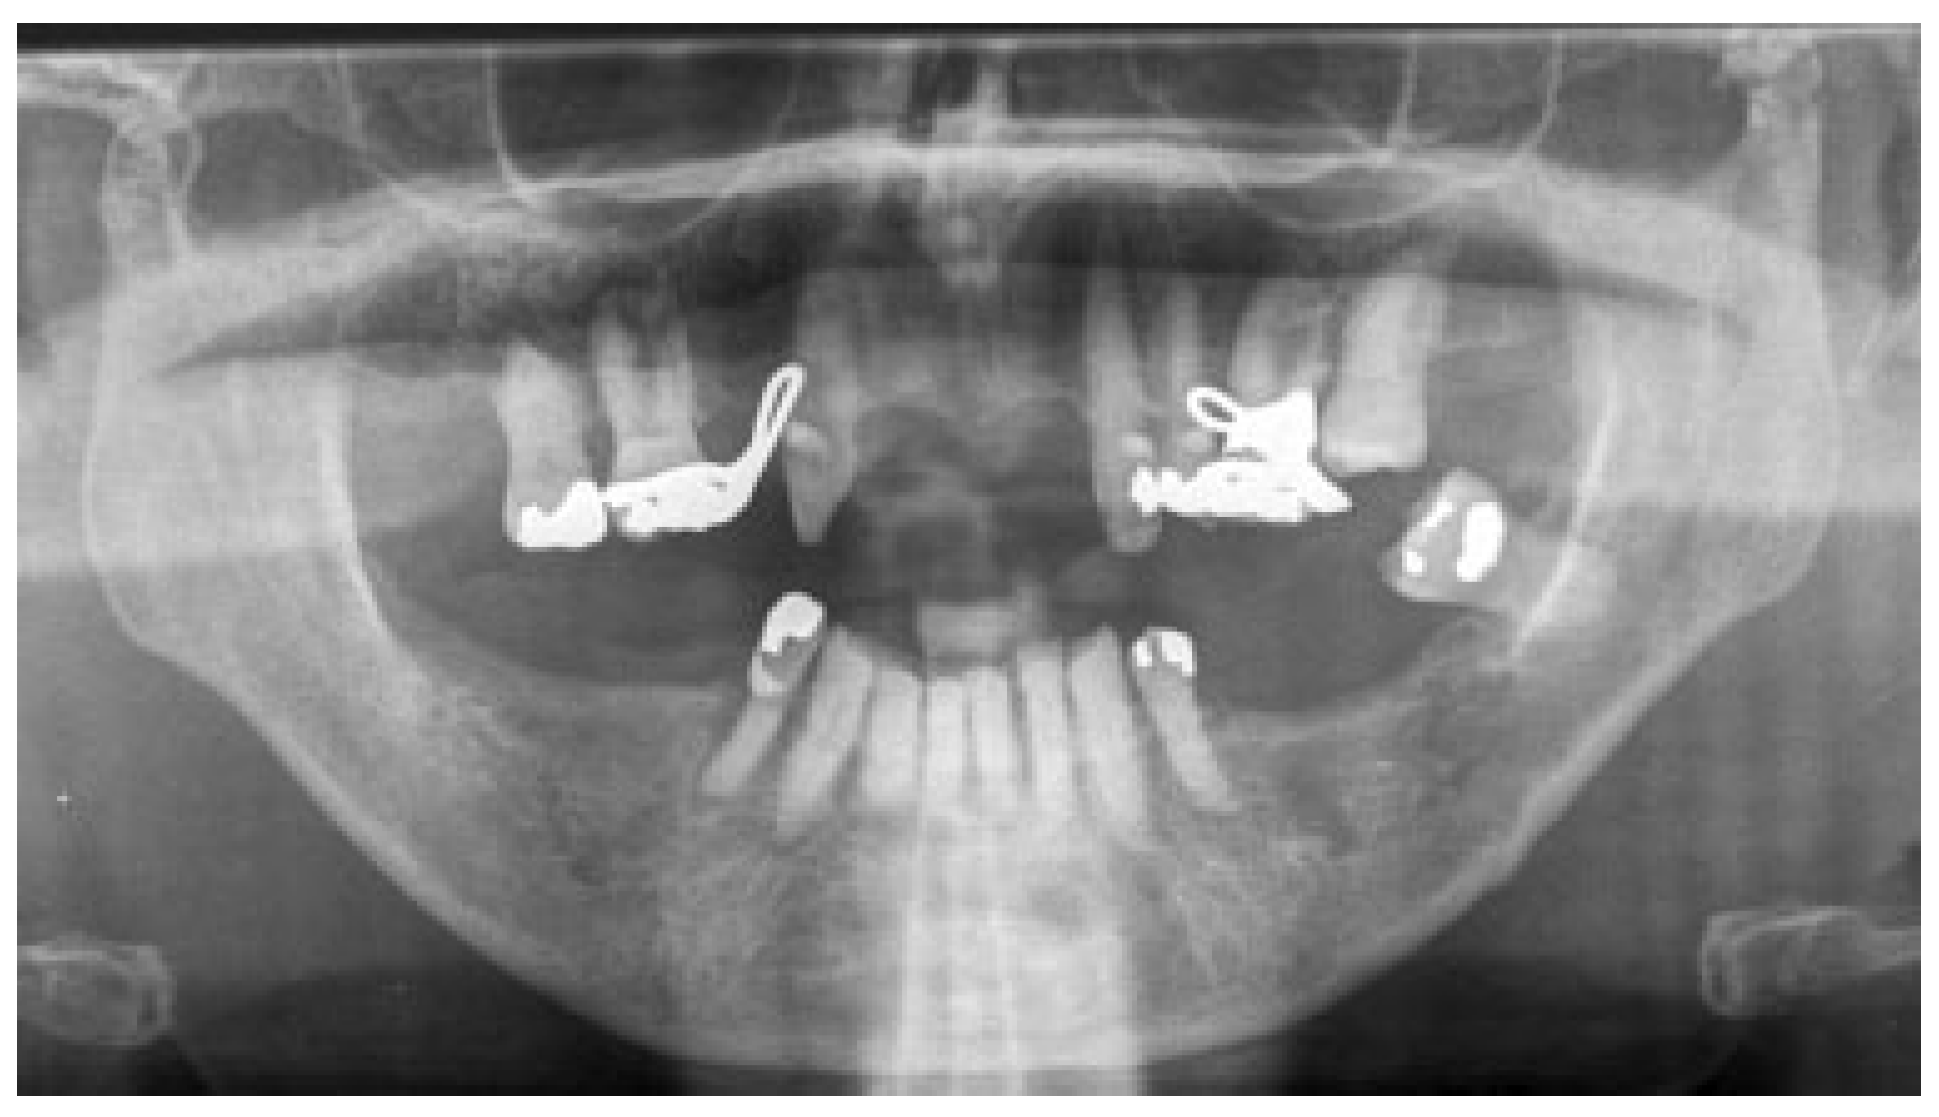

2.1. Case 1

2.2. Case 2